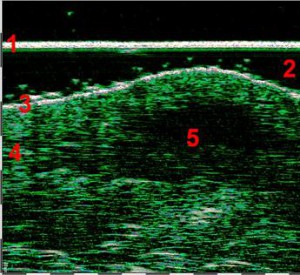

-Υπέρηχος Υψηλής Συχνότητας (HFUS) και Ιστολογία

-Απλά διαγνωστικά κριτήρια κακοήθειας όγκου δέρματος

-Μελάνωμα

-Μέτρηση επιπέδων Breslow και Klark σε έμβιο οργανισμό (IN VIVO)